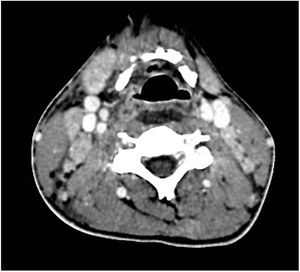

Se objetiva una colección laminar de 7,5×3,3×0,9cm, de paredes hipercaptantes, en espacio retrofaríngeo, extendiéndose desde C2 a C6 (fig. 1), y múltiples adenopatías laterocervicales bilaterales de aspecto reactivo (fig. 2). Con el hallazgo de posible absceso retrofaríngeo, se contacta con el servicio de otorrinolaringología, que decide ampliar el espectro de antibioterapia asociando meropenem y clindamicina, y manejo quirúrgico. Se realiza faringotomía posterior, con punción en diferentes puntos de la pared posterior, sin obtener material para cultivos.